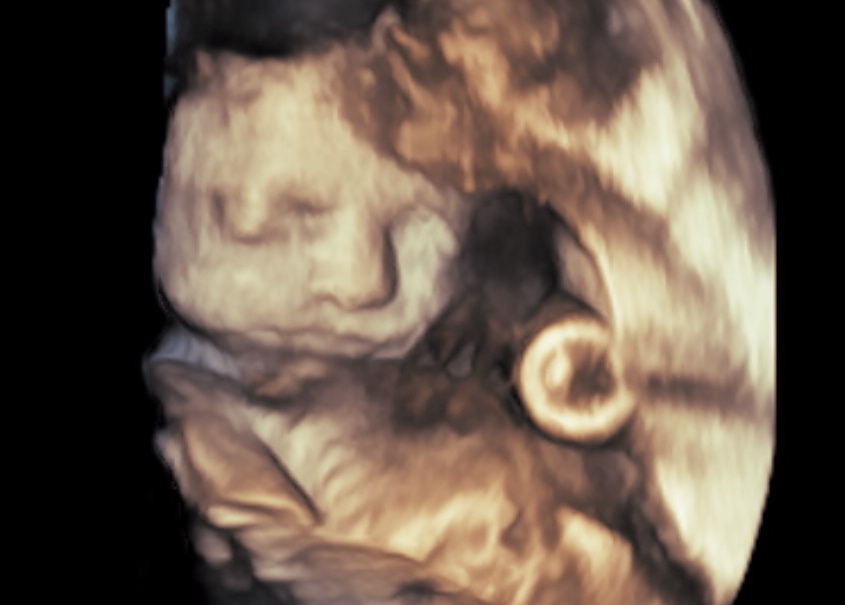

Saw maternal/fetal today and everything is good with baby - she looks so cute and her anatomy is looking great!

Obviously, I will do ANYTHING to keep this LO cooking as long as possible so she is as healthy as she can be, I'm just bummed that I can't be as active as I'm used to. In the meantime, I think I'll keep looking at her sweet face!